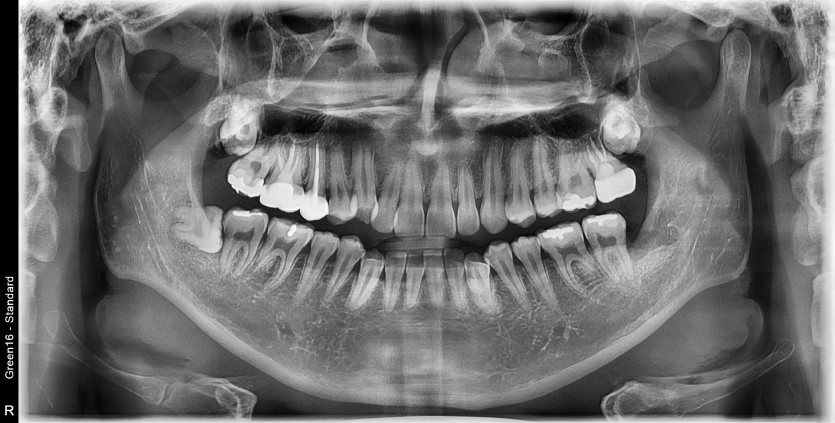

#38 사랑니 발치

구강 외과 전문의가 당일 발치했습니다.